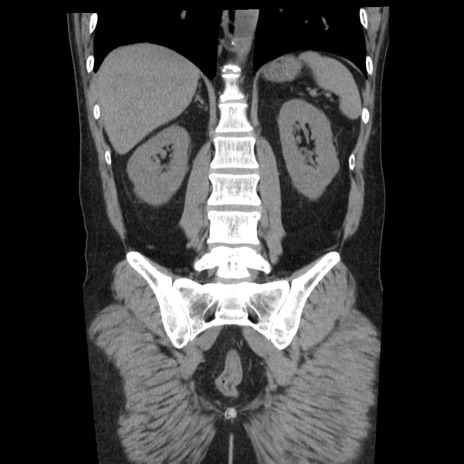

症例29(冠状断像)

【症例】40歳代男性

【現病歴】2日前から胃痛あり。徐々に周期的な激痛に変化した。本日になっても激痛があるため受診。

【身体所見】意識清明、BT 38-39℃台あり、腹部:膨満、やや硬、右下腹部に圧痛あり。

【データ】WBC 8500、CRP 23.26